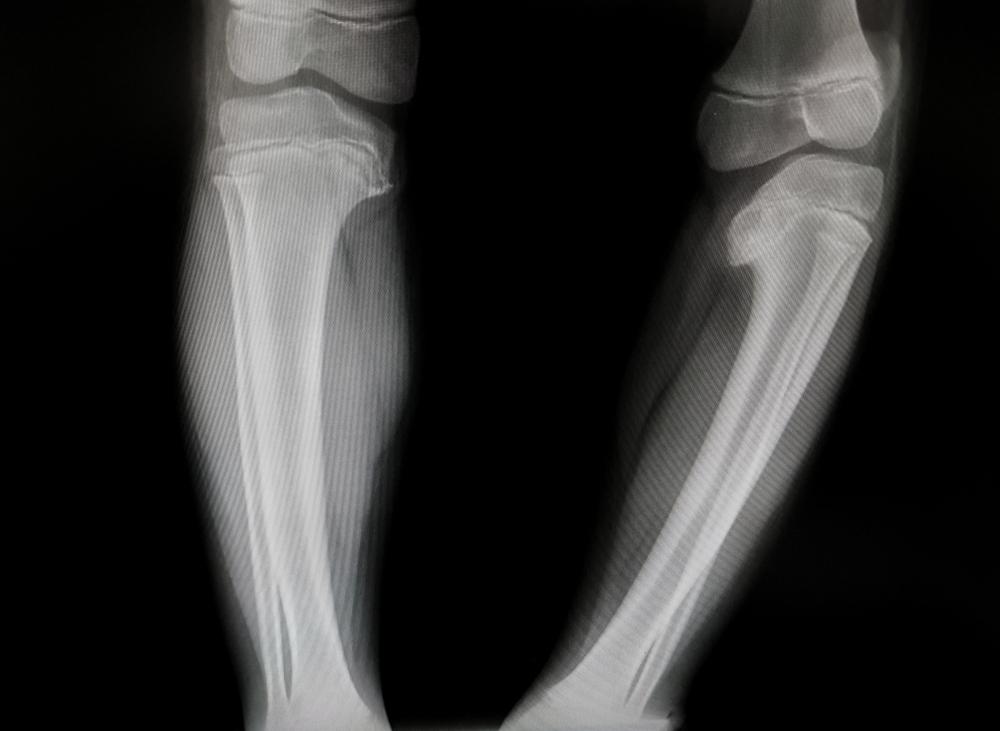

Untuk memastikan kondisi yang dialami, dokter juga akan menjalankan pemindaian dengan foto Rontgen.

Pemindaian ini bertujuan untuk membantu dokter melihat pertumbuhan tulang anak dan mendeteksi penyebab kebengkokan pada tulang.

Pemeriksaan baru perlu dilakukan pada anak di atas usia 2 tahun. Ini karena anak

di bawah usia 2 tahun bisa memiliki kaki yang bengkok secara alami dan bukan menandakan kelainan bentuk kaki.

Jika bentuk kaki anak masih bengkok setelah memasuki usia 2 tahun, dokter akan menyarankan pemeriksaan untuk memastikan kondisi kaki anak.